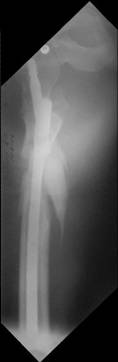

Congratulations. Virtually perfect. What reduction technique did you use? Looks like still traction table? To cavil to at least something looks like reduction is in microscopic varus - comparative x-rays can clear this - though only for academic interest with no clinical significance. Did you insert distal screws?

To obtain clear lateral view - with x-ray tube set to AP view perform hip and knee flexion 90/90 and some abduction, with no rotation.